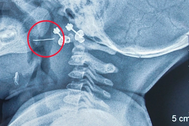

Trong quá trình tiến hành phẫu thuật nội soi ổ bụng cho người bệnh, các bác sĩ phát hiện có một lỗ thủng ruột non ở cách góc hồi manh tràng 20mm. Mở tổn thương kiểm tra bác sĩ thấy một dị vật giống mang cá đâm thủng thành ruột từ trong ra ngoài, xung quanh lỗ thủng ruột được bao phủ nhiều giả mạc và dịch đục.

Dị vật đâm thủng ruột non của bệnh nhân (Ảnh: Bệnh viện cung cấp).